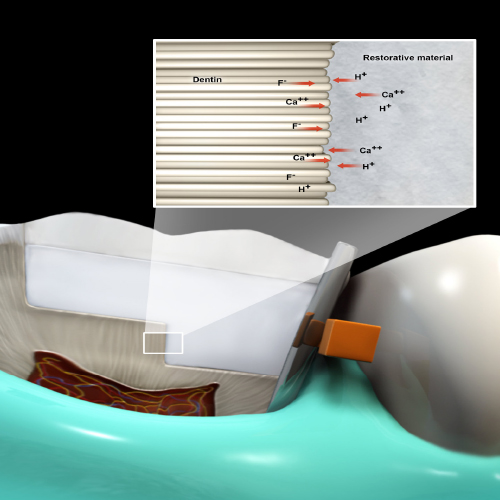

Bioactive Dental Materials: The Future Is Now

Wednesday, July 28, 2021

This Compendium eBook features a continuing education (CE) article that describes how the recent development of bioactive dental materials has increased the longevity of dental restorations and improved clinical outcomes after dental procedures.